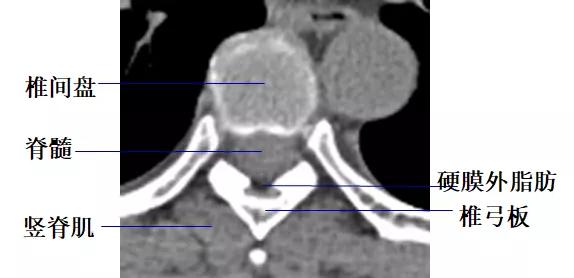

2.椎管及内容物

硬膜外脂肪:低密度影。

硬脊膜囊:呈圆形或椭圆形软组织密度影。CT平扫不能区别硬脊膜囊、脑脊液和脊髓。

3.椎间孔

位于椎管前外侧,其内的脊神经根呈软组织密度,周围有低密度的脂肪组织环绕。

4.椎间盘

由髓核、纤维环、软骨板和Sharpey纤维环构成呈软组织密度影,CT值为70±5HU,不能区分髓核和纤维环。